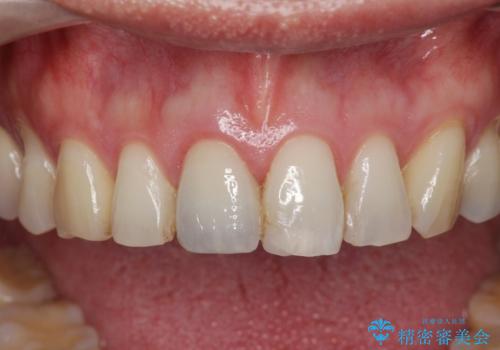

目立つ前歯の審美性が改善したことで見た目を気にせず笑えるようになった。との嬉しい感想をいただくことができました。

感染の疑われる根管内に対し再度根管治療を行い、セラミッククラウンを作製することで審美性の回復します。